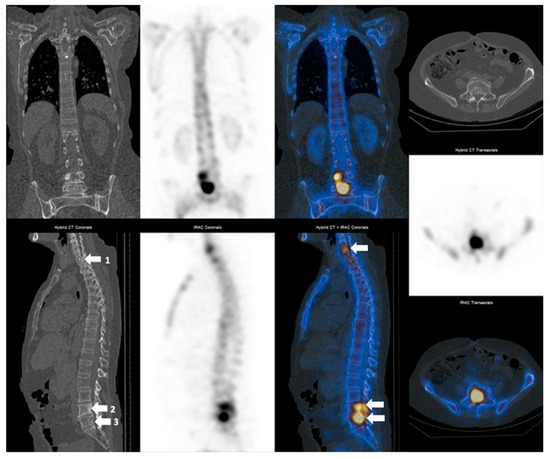

3.2. SPECT-CT SUVmax in Metastatic Lesions and Degenerative Bone Disease

3.3. SUVmax Cutt-off Value in Differentiating between Degenerative and Metastatic Lesions